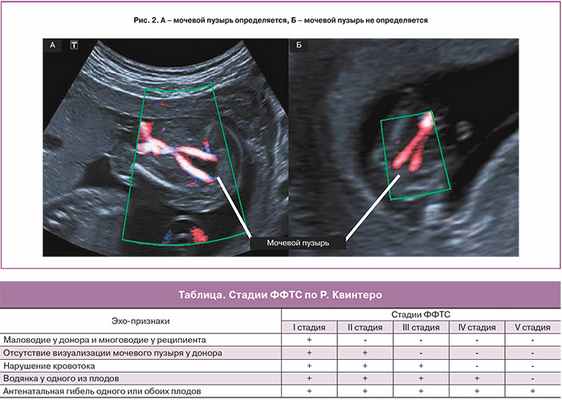

На основании эхографических признаков ФФТС Рубен Квинтеро с соавт. [6], в 1999 году, предложили классификацию (таблица), которая получила широкое распространение и используется во всем мире.

I стадия ФФТС характеризуется наличием маловодия плода донора (МВК менее 2 см) и многоводия реципиента (МВК более 8–10 см) (рис. 1).

II стадия является отражением дальнейшего прогрессирования заболевания. К описанным выше признакам выраженного различия количества амниотической жидкости близнецов присоединяется отсутствие визуализации наполнения мочевого пузыря донора (рис. 2). Некоторые исследователи утверждают, что наличие небольшого мочевого пузыря донора, не наполняющегося на протяжении ультразвукового исследования, также следует расценивать как II стадию ФФТС [8].